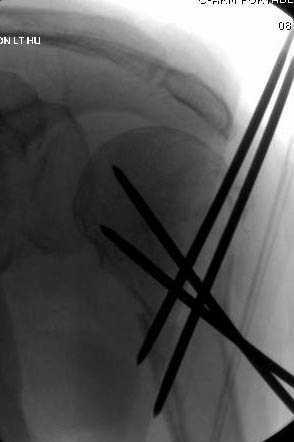

Наш недавний случай перкутанной фиксации "методом

Сиэтла" спицами 2.8 мм с резьбой на конце.

Головка плечав небольшом варусе или это проекционное?

-Головка плеча в небольшом варусе или это

проекционное?

Да, там имеем небольшой варус, надеемся, что в будущем проблемы не будет.

Из-за большого обьема конечности доступ к бугорку был затруднен, предварительно зафиксированный шуруп не удержал бугорок, поэтому фиксацию провели толстыми нитками. Состоятельность фиксации бугорка обычно проверяем во время операции, под рентген контролем проводится движения конечности, особенно приведение.